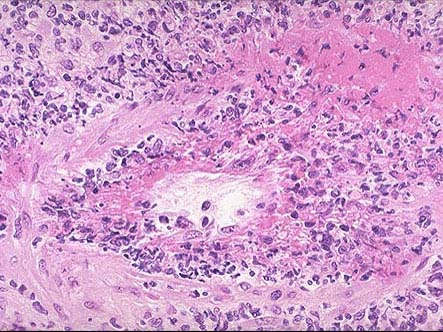

韦格氏肉芽肿患者病变部位镜下可出现如图所示改变,下列关于该病说法错误的是()。

[单选题]韦格氏肉芽肿患者病变部位镜下可出现如图所示改变,下列关于该病说法错误的是()A . 30~50岁多见,男性略多B . 在动脉壁、动脉周围或血管外部区域出现肉芽肿炎症C . 多数患者出现不同程度的肾小球肾炎D . 肾脏病变常为局灶坏死性肾小球肾炎伴新月体形成E . 严重者可引起急性肾功能衰竭